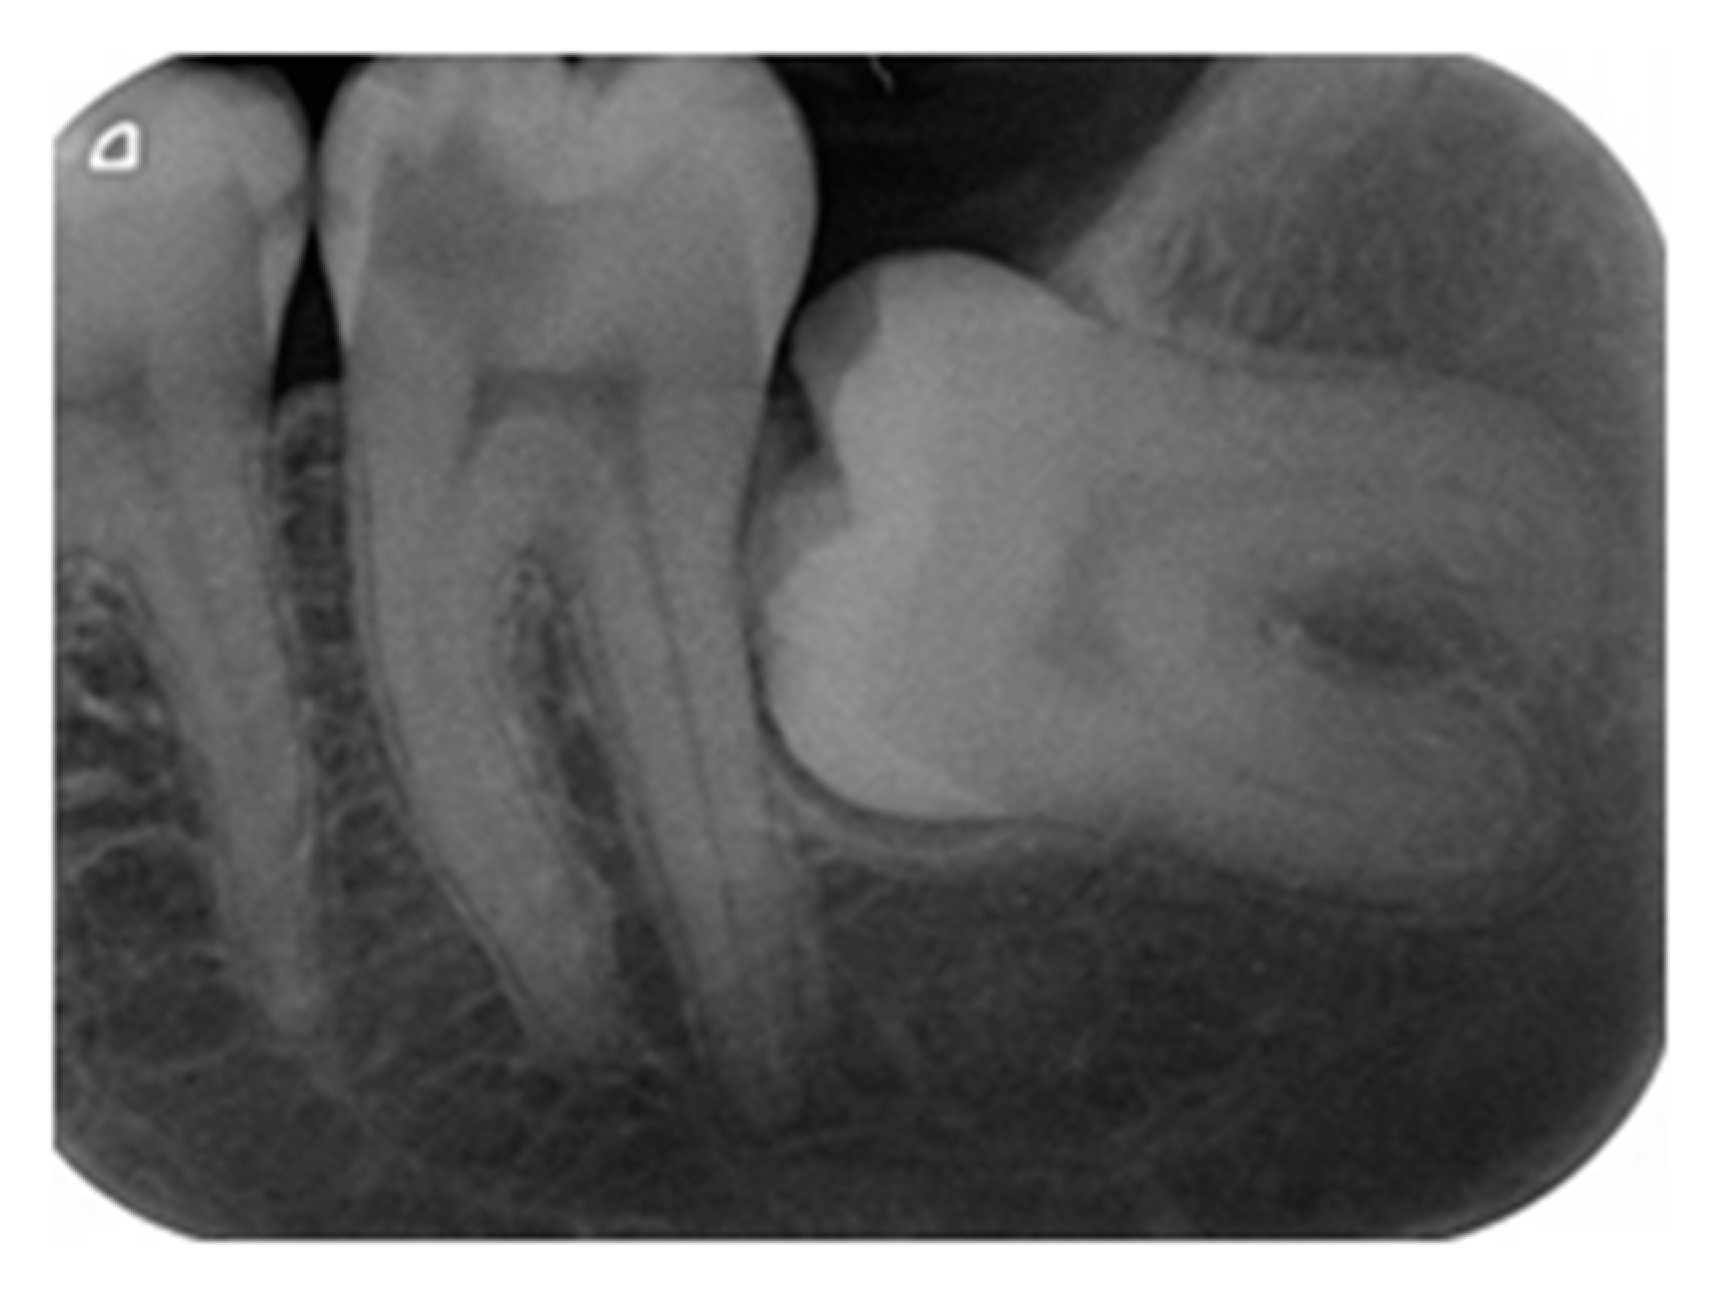

4.3. Endpoint of Carious Dentine Excavation

- Demant, S.; Dabelsteen, S.; Bjørndal, L. A macroscopic and histological analysis of radiographically well-defined deep and extremely deep carious lesions: Carious lesion characteristics as indicators of the level of bacterial penetration and pulp response. Int. Endod. J. 2021, 54, 319–330. [Google Scholar] [CrossRef]